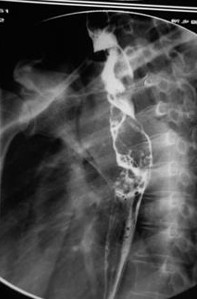

病例1 女,51歲,以“進(jìn)行性吞咽困難1年”為主訴于2007年2月19日入院。鋇餐造影、胃鏡示食管上段占位性病變,確診為食道鱗癌(圖1),拒絕手術(shù),行放療+今又生治療。食道鏡下瘤內(nèi)注射今又生,1×1012VP/次/周×6,…